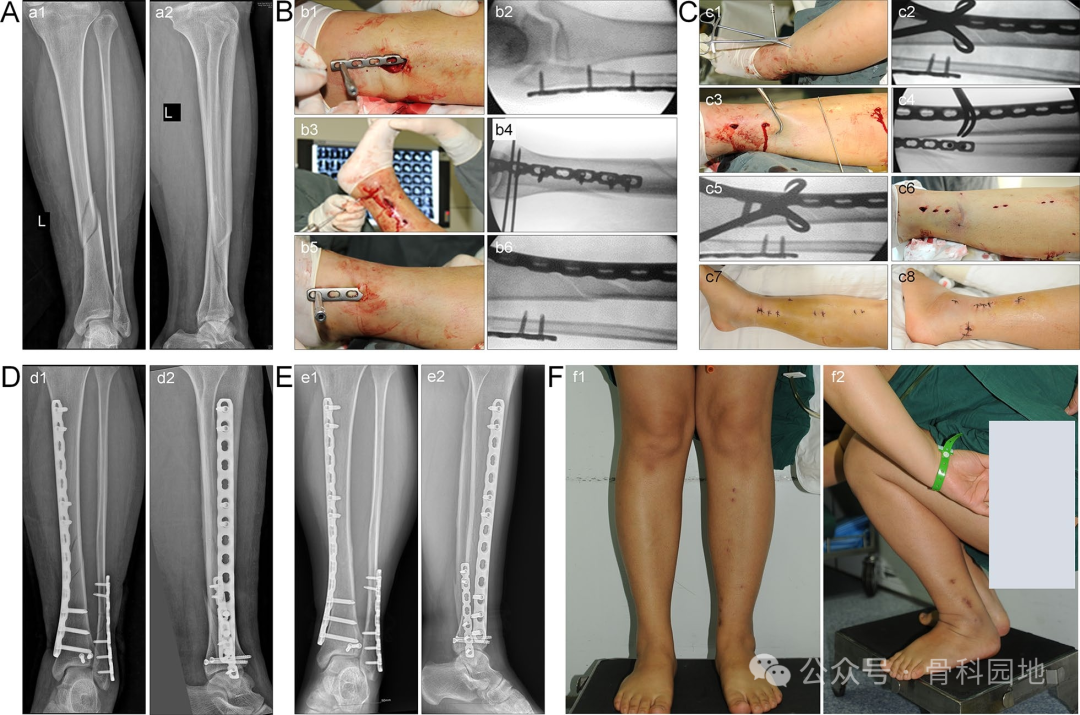

下图中的患者患有胫骨、腓骨和后踝骨折(图A)。在固定腓骨和后踝后,通过钢板辅助的经皮夹持技术有效地纠正了胫骨外侧移位(图B,C)。治疗后,患者获得了良好的骨折复位、骨愈合和功能恢复情况(图D-F)。